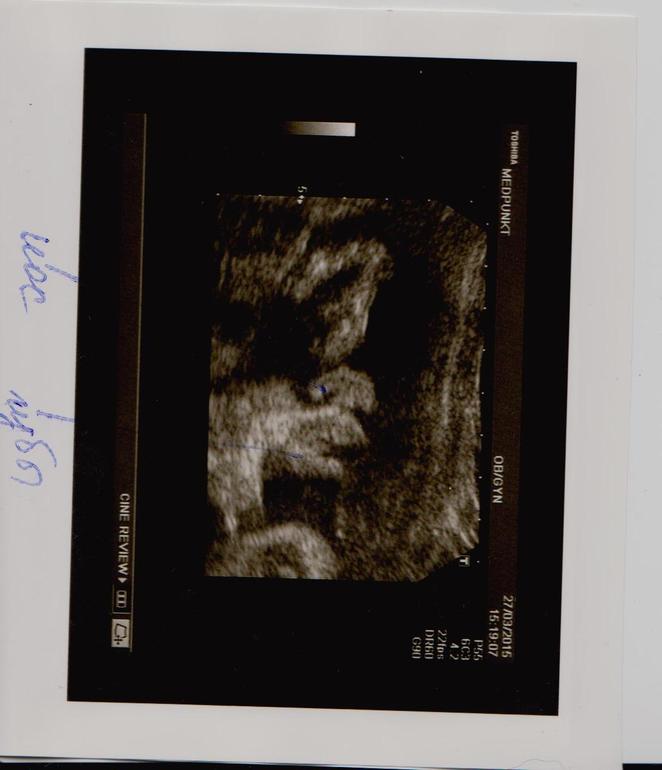

Сейчас подходит к концу уже 31 неделька. Только сегодня мы узнали что оказывается ждем мы принцессу-скромницу, которая все это время упорно прятала свои прелести от узисток! Малышка видимо все таки вняла мольбам родителей и показалась нам во всей красе

наша сладенькая. Муж говорит "вся в мать", зато ножки явно папины)) фото прилагаются))